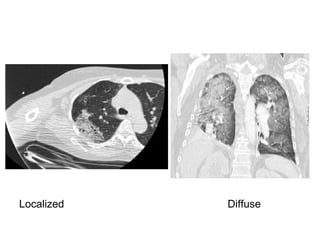

1-Diffuse pulmonary hemorrhage

Localized Diffuse